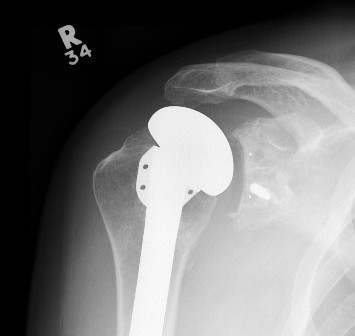

TSR Loose glenoidaTSA loose glenoid

Glenoid Component LooseningHumeral resurface loose

Schoch et al. JSES 2019

- 492 aTSA at 5 year follow up

- 308 (63%) had no radiolucent lines

- 184 (37%) had peri-glenoid lucency

- those with glenoid lucency had decreased ROM and patient-reported outcomes